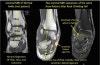

MRI : 발목 염좌(Medial ankle sprain)